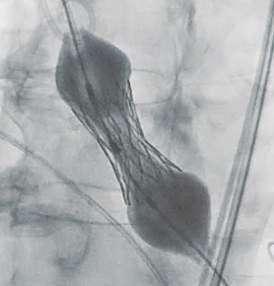

Navigator with Myval THVNavigator balloon with dual expansion ports at each end ensures rapid, simultaneous, controlled expansion (dog-boning) of distal and proximal ends

This typical dog bone pattern of inflation steadies the valve during expansion phase, ensuring its precise annular position and deployment without any risk of valve migration